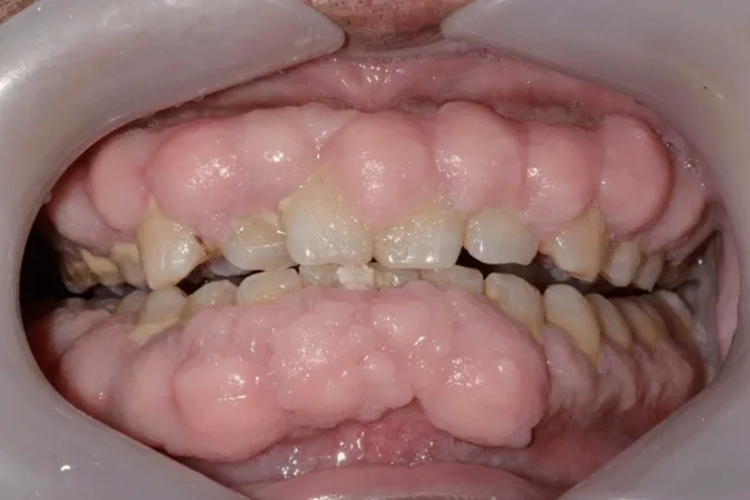

药物性牙龈增生:药物性牙龈增生主要表现为龈乳头呈球状、结节状,增生的牙龈表面可呈桑葚状或呈分叶状,形似菜花状,增生的牙龈基底与正常牙龈之间可有明显的沟状界限。增生的牙龈组织一般呈淡粉红色,质地坚韧,略弹性,不易出血,多数患者无自觉症状。

牙龈瘤:牙龈瘤以女性较多,以青年及中年人为常见。肿块一般较局限,呈圆形或椭圆形,有时呈分叶状,形似菜花状,大小不一,直径由几毫米至数厘米。肿块有的有蒂,如息肉状,有的无蒂,基底宽广。